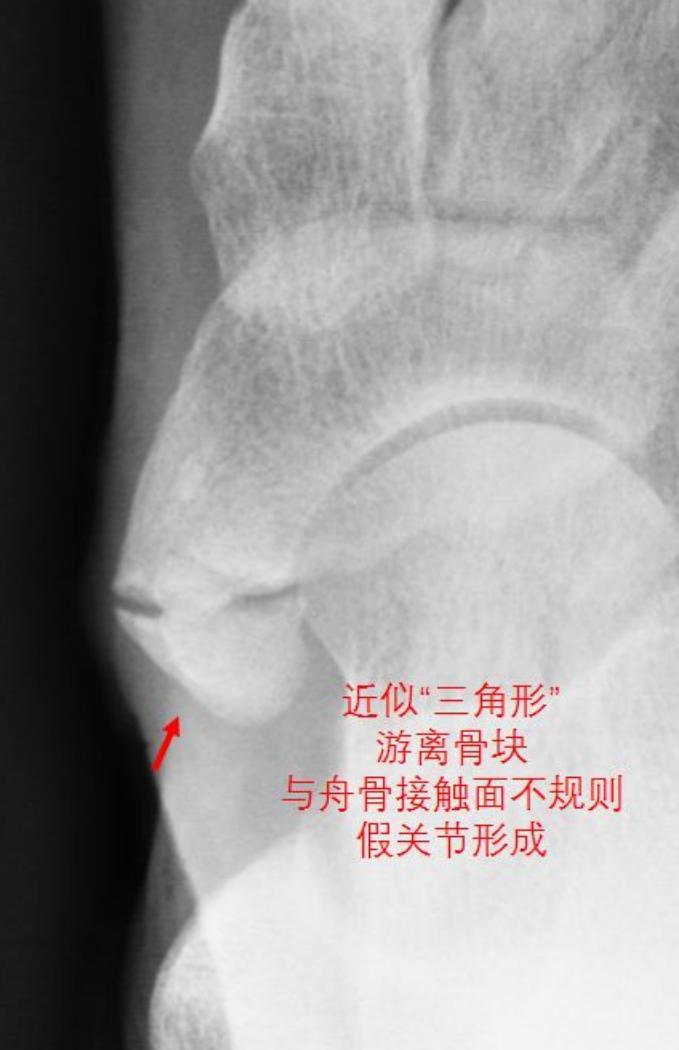

II型:假关节型,X线上表现副舟骨骨化中心,近似"三角形"或者"心形"骨块通过软骨联合附着于舟骨,形成假关节,此类型的胫骨后肌腱通常附着于副舟骨,是足内侧疼痛的常见原因之一。